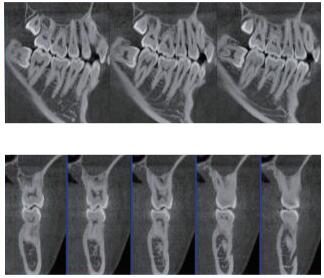

三維重建任意斷層

專(zhuān)有三維重建算法,可提供任意位置高清斷層影像。

多平面組合重建

可同時(shí)觀察軸向面、冠狀面和矢狀面圖像,方便臨床診斷。